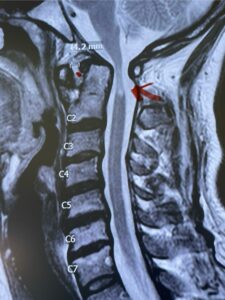

Fig. 4a: Sagittal T2-weighted cervical MRI demonstrating severe cord compression with myelomalacia of upper cervical spinal cord (red arrow). Notice the increased atlanto-dens interval (red dot).

Fig. 4b: Axial T2-weighted cervical MRI demonstrating severe spinal cord compression from atlanto-axial instability (red arrow)

This is a 42 year-old female who presents with severe progressive weakness and numbness and difficulty with balance over a 6-month period. She has a history of having a motor vehicle accident at 5 years old but was never imaged. On exam she was noted to be severely myelopathic. Imaging revealed severe spinal cord compression at the level of C1 (Figs 4a and b).

Cervical x-rays revealed a significantly increased atlanto-axial interval (Fig. 5) On review of her imaging studies it was noted that the right C2 isthmus was very thinned by the vertebral foramen (Figs 6a, b, and c) which would make an attempt at placing a C2 pars screw dangerous. A decision was made to perform an occipital-cervical fusion because only possible unilateral fixation and an extensive C1 laminectomy to be performed eliminating a fixation point if a more traditional C1-C2 was performed. Even if C1 lateral mass screws were able to be placed one could only perform a unilateral screw construct fixation to C2. We performed an occipital cervical fusion down to C4 to get enough inferior fixation and C1 laminectomy. The decompression went well. We placed a left unilateral pars screw and bilateral C3 and C4 lateral mass screws. We placed three 12 mm screws in the midline keel (Fig. 7). Postoperatively the patient had all around improvement in her symptoms and did not qualify for rehab. Her post op films at 6 weeks (Fig. 8)